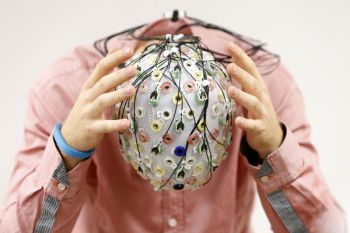

Para peneliti Amerika Serikat menemukan bukti fisik penting bahwa tidur bisa memperkuat ingatan.Dalam hasil studi yang ...

Ilmuwan Swedia menemukan bukti bahwa tidur dapat membantu meningkatkan kesehatan sel-sel otak yang dimuat dalam jurnal ...